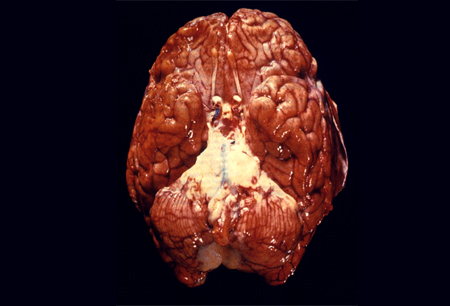

ბაქტერიები აღწევენ ცენტრალურ ნერვულ სისტემაში ჰემატოგენური გავრცელებით (ყველაზე გავრცელებული გზა) ან უშუალო გავრცელებით მიმდებარე უბნიდან, როგორიცაა პარანაზალური სინუსები ან დვრილისებრი ძვალი. ახალშობილებმა პათოგენები დედის არასტერილური გენიტალური სეკრეტებიდან, პლაცენტიდან ან ირგვლივ მდებარე არეებიდან შეიძლება შეიძინონ.[9] სუბარაქნოიდულ სივრცეში შესვლის შემდეგ ბაქტერიების გამრავლება სწრაფად ხდება. თავზურგტვინის სითხეში ბაქტერიული კომპონენტები იწვევს სხვადასხვა ანთებითი მედიატორების წარმოქმნას, რაც, თავის მხრივ, ხელს უწყობს თავზურგტვინის სითხეში ლეიკოციტების შემოდინებას.[24] ანთებითი კასკადი იწვევს ცერებრალურ შეშუპებას და ინტრაკრანიალური წნევის მომატებას, რაც ხელს უწყობს ნევროლოგიურ დაზიანებას და სიკვდილსაც კი.[Figure caption and citation for the preceding image starts]: ადამიანის თავის ტვინის ვენტრალური ხედი, რომელიც აჩვენებს Streptococcus pneumoniae-ით გამოწვეული ჩირქოვანი ბაზილარული მენინგიტის ინფექციასგამოსახულება მოწოდებულია აშშ დაავადებათა კონტროლისა და პრევენციის ცენტრის საზოგადოებრივი ჯანმრთელობის გამოსახულებების ბიბლიოთეკის მიერ [Citation ends].